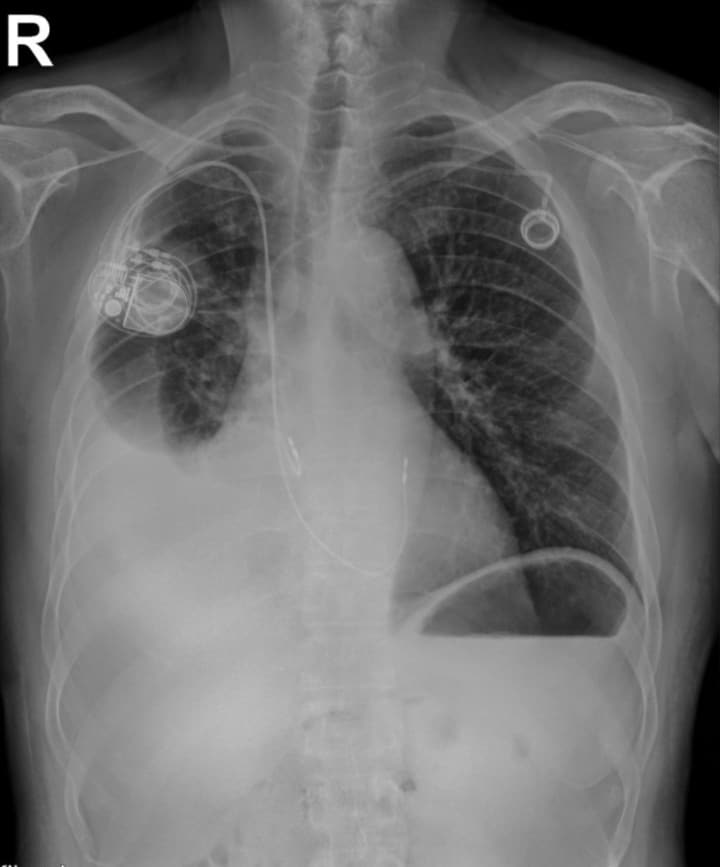

In this study, the dual energy soft tissue image revealed a suspicious soft tissue mass. In this case, the mass was overlapping the in-dwelling device (pacemaker).